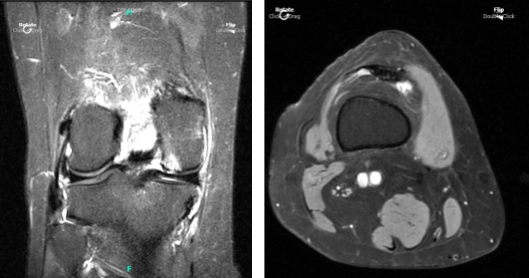

Patient returned to our office a week after the initial visit. Presented bilateral X-rays. Left knee demonstrates small full-thickness cartilage defects of the medial with inferior aspect of the lateral patellar facets with underlying patchy subchondral bone marrow edema.

Small partial-thickness cartilage defects on the medial trochlear facet. Small partial thickness cartilage loss central aspect of the medial femoral condyle with underlying small faint subchondral bone marrow edema. Small joint effusion and intact cruciate and collateral ligaments.

Her MRI right knee showed impression as follows: full-thickness cartilage defect inferior aspect of the lateral patellar facet and small full-thickness cartilage fissures of the medial patellar facet with underlying subchondral bone marrow edema.

Small full-thickness cartilage fissure of the medial trochlear facet with underlying small subchondral edema. Small full-thickness cartilage defects central aspect of the medial femoral condyle with underlying small subchondral bone marrow edema. Small to moderate joint effusion. Trace popliteal cyst.